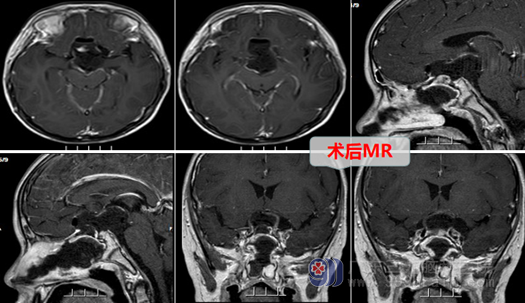

因为小袁已经双眼几近失明,所以加急,在入院的第三天医生就为小袁在全麻下进行了手术,手术方式选择的内镜扩大经鼻蝶鞍上区颅咽管瘤切除术,这属于微创手术,不需要开颅,所以恢复起来比较快。术中扩大经蝶,在内镜直视下,精细分离肿瘤囊壁,解除肿瘤对视神经-视交叉的压迫,并且保护好下丘脑与垂体柄。并且手术很成功,术后的MR提示原病灶已经切除,病理结果提示:造釉细胞型颅咽管瘤,CNS WHO 1级。